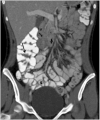

Results: The most common presenting symptoms were abdominal pain, bloody diarrhea and rectal bleeding. EC was characterized as a dense and predominantly eosinophilic inflammatory infiltrate in the lamina propria or epithelium without granulomas. CT scans were abnormal in six children (86%), demonstrating colonic wall thickening, predominantly cecal, in five (71%), mild to moderate terminal ileal thickening in two (29%), and pneumatosis in one (14%). Right colonic involvement was greater than terminal ileal involvement.

Conclusion: CT imaging findings in children with EC include right colonic wall thickening of variable extent downstream and absent or mild involvement of the terminal ileum. EC should be considered in the differential diagnosis in children presenting with abdominal pain and bloody diarrhea.